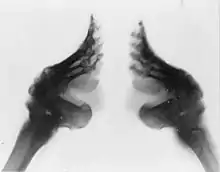

At the beginning of the binding, many of the foot bones would remain broken, often for years. However, as the girl grew older, the bones would begin to heal. Even after the foot bones had healed, they were prone to rebreaking repeatedly, especially when the girl was in her teenage years and her feet were still soft. Bones in the girls' feet would often be deliberately broken again in order to further change the size or shape of the feet. This was especially the case with the girl's toes, which were broken multiple times as small toes were especially desirable.[86] Older women were more likely to break hips and other bones in falls, since they could not balance securely on their feet, and were less able to rise to their feet from a sitting position.[87] Other issues that may have arisen from footbinding included paralysis and muscular atrophy.[83] By the turn of the century, footbinding had been exposed in photographs, X-rays, and detailed textual descriptions. These scientific investigations detailed how footbinding deformed the leg, covered the skin with cracks and sores, and altered the posture.[88]